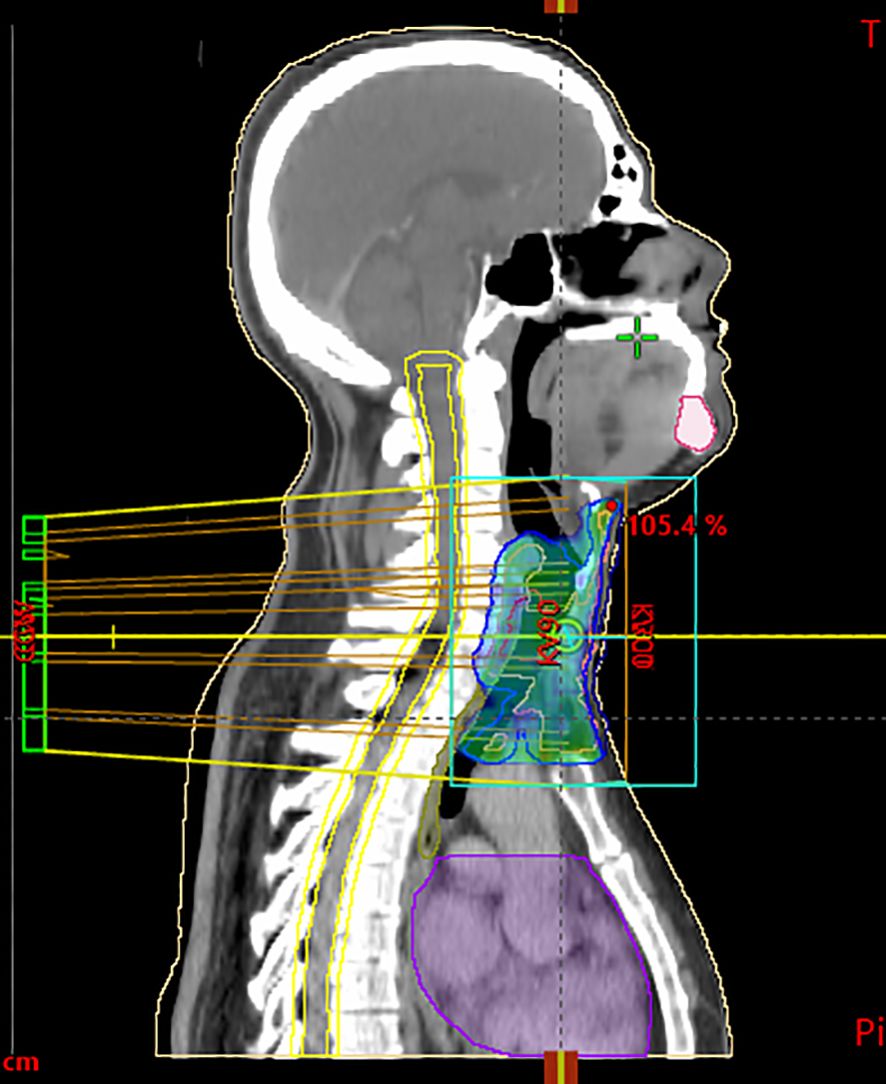

According to the pathological exam, adjuvant radiotherapy was decided at a multidisciplinary team meeting. The clinical target volume was delineated as the gross tumor volume with a 1-cm margin, including the mediastinal structures. A dose of 60 Gy for planning treatment volume in fractions of 2 Gy was administered based on 6-MV X-ray with volumetric modulated arc therapy. Maximum spinal cord dose was 29.5 Gy (Figure 3). Volume of the esophagus receiving 60 Gy was 2.5% and a mean dose of 38.7Gy. Radiotherapy was completed in August 2023, and since then, the patient remains in observation.

Figure 3. Sagittal CT scan used for radiotherapy planning, showing target volumes and isodose distribution. The blue/green areas represent the clinical target volume (CTV) and planning target volume (PTV), including the primary tracheal tumor and safety margins. Yellow lines delineate isodose curves, illustrating the percentage of the prescribed dose (95%, 100%, 105%) delivered to the tumor region. The violet contour corresponds to an organ at risk (OAR), delineated to monitor dose exposure.